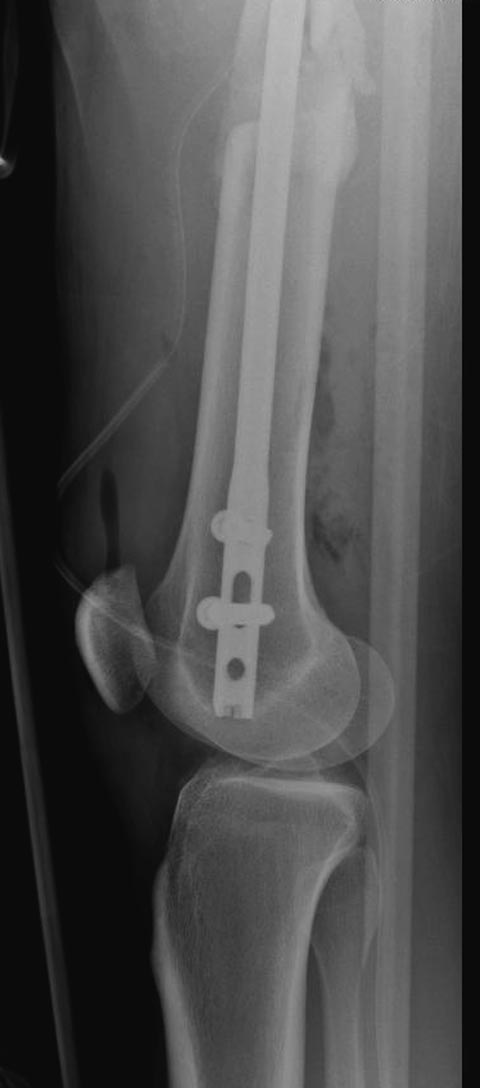

Здесь выставлен ренгенограммы больного, ему 21, травму получил в результате высокоскоростной погони на украденной машине, которая закончилась смертью трех остальных “боевых комрадов”. Начатую коллегой открытую операцию на шейке пришлось закончить мне, установкой винтов и ретроградной фиксацией бедра. Выписка в обычное сроки и наблюдался амбулаторно. Каждый раз напоминали о возможности осложнений ввиде несращения! По истечению 4 месяцев появились признаки варусной деформации. На СТ срезах несращение шейки и бедра. Риминг, замена на более толстый гвоздь и вальгусная остеотомия.